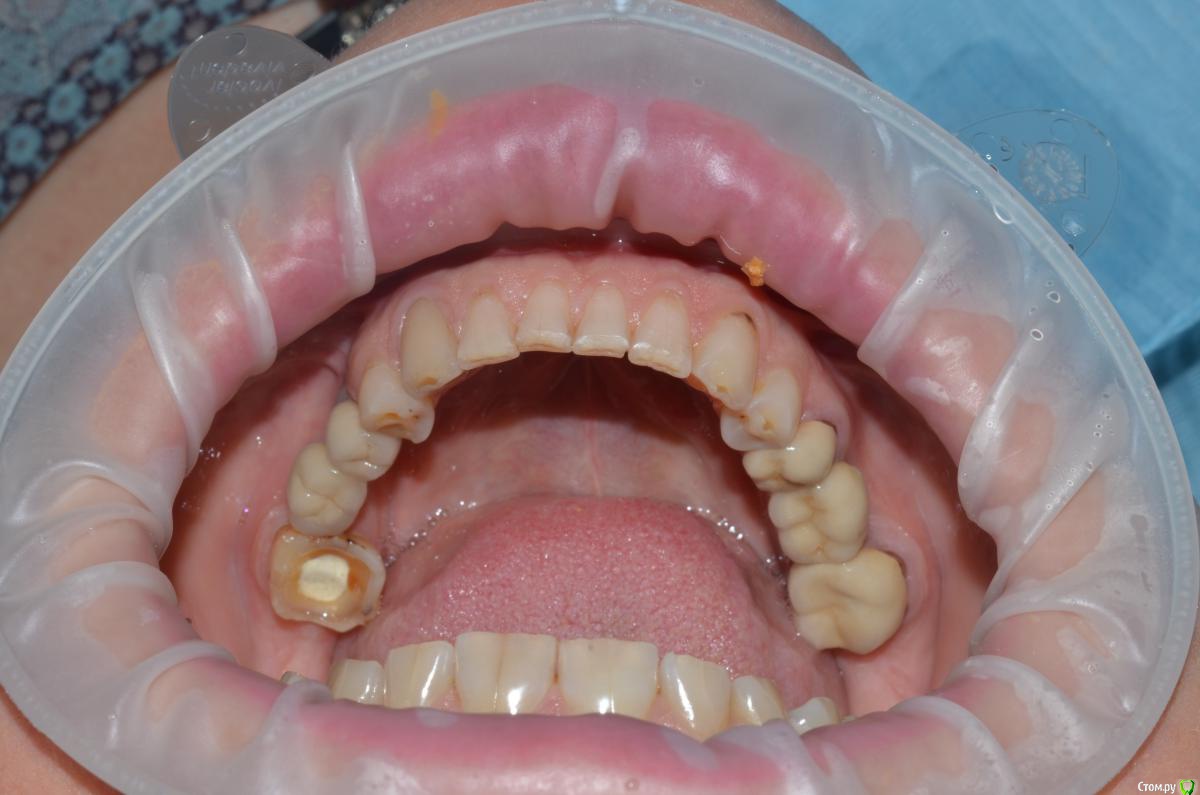

NazranDantist Опубликовано 4 сентября, 2015 Автор Поделиться Опубликовано 4 сентября, 2015 Продолжение кейса. Работа еще не закончена, зуб 25, 35, 36 - аббатменты на подходе, поэтому решили сделать после отпуска пациентки. Фото протокол не соблюдал, курс рубля прыгал, торопился в обменник . Вся работа - имакс на Цереке с редуцированием, фиксация - фронт на чойс, боковые - У-200. Ссылка на комментарий

CHEREDNICHENCO Опубликовано 12 сентября, 2015 Поделиться Опубликовано 12 сентября, 2015 Режет глаз смещение цл, оптг необходимо определенно, хотя бы для оценки состояния тттз и периапикальных тканей в 4 секторе.... Индикатор кариеса используете в работе???.... А зачем в 3 секторе оставили временную конструкцию?! Или это постоянная???..... В десятых- эстетически не вяжется соотношение нижних к верхним... PS: В связи с определенным географическим положением, КНДР находиться в 1 км. 44 м. от места моей работы! и хочу сообщить Вам,- уровень их работ растет от из года, в год! Ссылка на комментарий

NazranDantist Опубликовано 12 сентября, 2015 Автор Поделиться Опубликовано 12 сентября, 2015 Режет глаз смещение цл, оптг необходимо определенно, хотя бы для оценки состояния тттз и периапикальных тканей в 4 секторе.... Индикатор кариеса используете в работе???.... А зачем в 3 секторе оставили временную конструкцию?! Или это постоянная???..... В десятых- эстетически не вяжется соотношение нижних к верхним... PS: В связи с определенным географическим положением, КНДР находиться в 1 км. 44 м. от места моей работы! и хочу сообщить Вам,- уровень их работ растет от из года, в год! А что делать с центральной линией, если она смещена? Кариес индикатор для чего? Про времянки в 3-ем секторе уже написал " Работа еще не закончена, зуб 25, 35, 36 - аббатменты на подходе". Оценка периапекальных тканей проводилась. Ссылка на комментарий

CHEREDNICHENCO Опубликовано 12 сентября, 2015 Поделиться Опубликовано 12 сентября, 2015 До протезирования, без смещения! 1.5, 1.6 кариес II класс, 4.3 - V. Как сагиттальную окклюзионную кривую выводили??? Не проще было подождать подхода аббатов...со времянками? Ссылка на комментарий